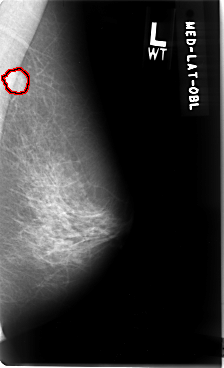

B_3032_1.LEFT_MLO

LEFT_MLO LINES 4776 PIXELS_PER_LINE 2904 BITS_PER_PIXEL 12 RESOLUTION 50 OVERLAY

FILE: B_3032_1.LEFT_MLO.OVERLAY

TOTAL_ABNORMALITIES 1

ABNORMALITY 1

LESION_TYPE MASS SHAPE ROUND MARGINS ILL_DEFINED

ASSESSMENT 4

SUBTLETY 5

PATHOLOGY MALIGNANT

TOTAL_OUTLINES 1